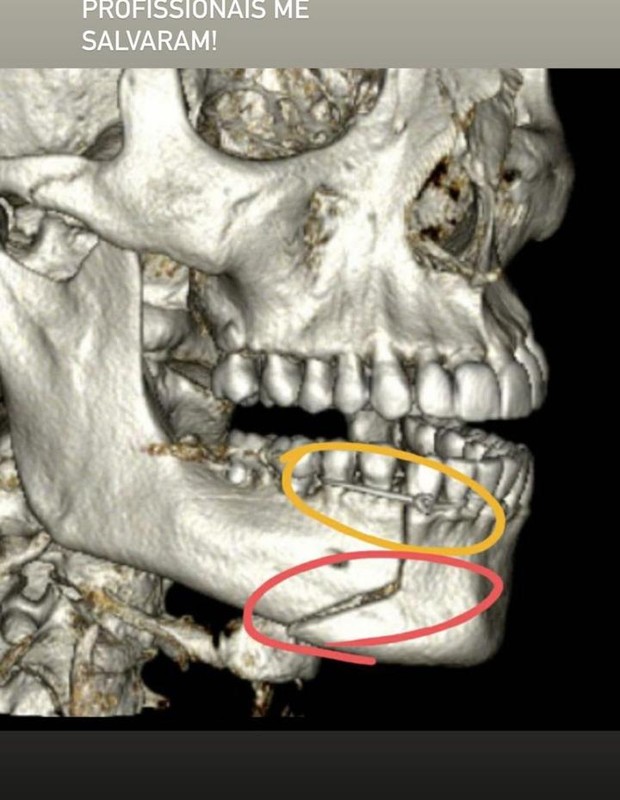

“Eu estava com alguns amigos e, do nada, fui puxado pelas costas, pelo pescoço, jogado no chão e agredido. Vítima de socos e chutes no rosto, que levaram a uma fratura exposta na minha mandíbula. A impressão que eu tinha é de que minha boca estava pendurada naquele momento”, relembra. “Os vídeos serão juntados ao processo. O médico e sua equipe optaram por amarrar a minha boca com um fio de aço para que eu fizesse a cirurgia em São Paulo e pudesse cumprir meus compromissos de trabalho”, detalha.

“Pensava apenas na minha família, nos meus filhos. Fiquei com muito medo de ficar com sequelas pra sempre. Minha boca ainda tá torta, e ainda está muito inchado, muito roxo”, mostra o ator.